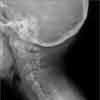

Radiograph of cervical spine as shown.

The clinical triad of low posterior hairline, short neck, and limited range of neck motion in a patient with fused multiple cervical vertebrae isdiagnostic of Klippel-Feil syndrome. Maurice Klippel and Andre Feil originally described the syndrome in 1912.1 These authors described a 46-year-old tailor who had an unusually short neck with marked restriction of neck movement. The patient had 4 fused cervical vertebrae.

Lateral flexion-extension radiographs of the cervical spine confirm the diagnosis and establish the range of motion of each open interspace.2 A lateral radiograph of the skull will demonstrate occipitocervical abnormalities.10 MRI of the cervical cord and craniocervical junction is indicated before any orthopedic procedure and whenever neurologic symptoms or signs are present in the upper extremities.17